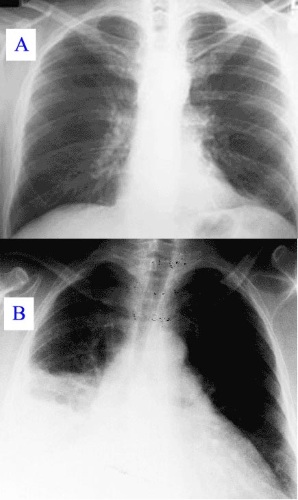

Рентгенография легких – наиболее эффективный метод диагностики, стоимость которого не превышает 300 руб.

Проводится в любом учреждении и помогает выявить локализацию очага поражения. Благодаря снимкам специалист может оценить степень поражения тканей.